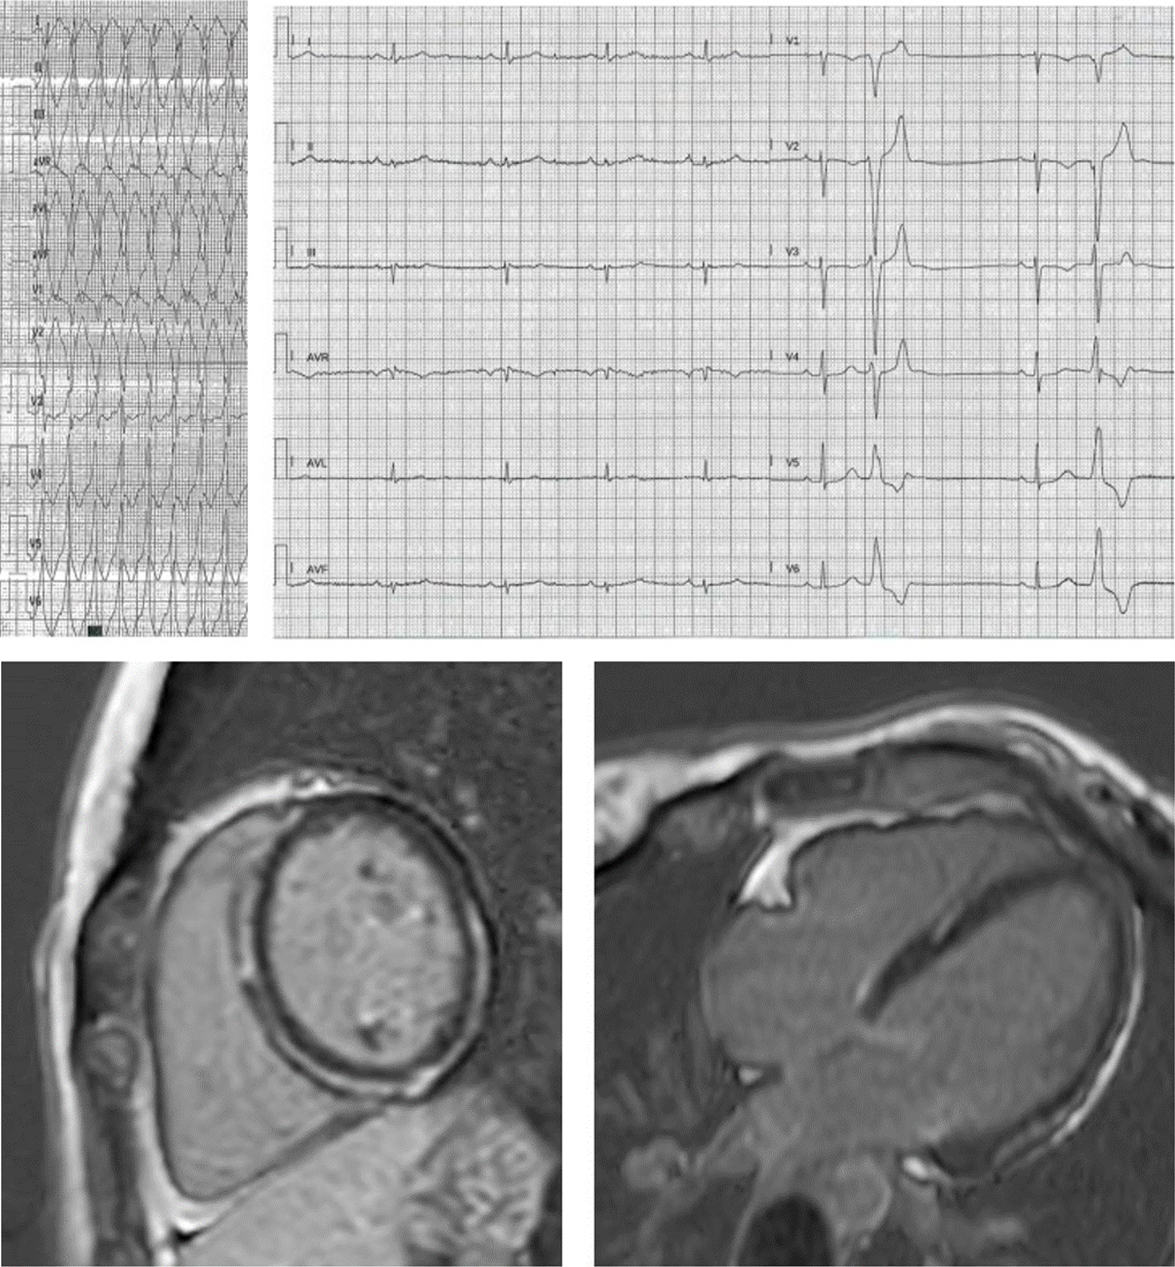

Fig. 2.Proband, aged 27 years, desmoplakin mutation: poorly tolerated monomorphic VT during training. See a midlayer ring-like fibrotic tissue involvement of the LV, without RV involvement. ECG shows low-amplitude limb leads with multifocal ventricular beats stemming from the anterior LV wall.

Fig. 3.Progressive fibrofatty replacement of the RV and later of the LV in a patient with PKP2 mutation, detected by serial ECG recordings (A) from age 44 up to 72, implanted in secondary prevention at 66 because of monomorphic VT at 210 bpm. Both ECG and CMR (B) show epicardial, midventricular and also transmural fibrotic involvement of the inferior and the posterior lateral LV wall, mimicking ischemic cardiomyopathy in the absence of coronary artery disease. The RV involvement and the progressive ECG changes along years (transition from a normal pattern to an RV and eventually to extensive LV involvement) hinted at genetic testing for the etiologic diagnosis.